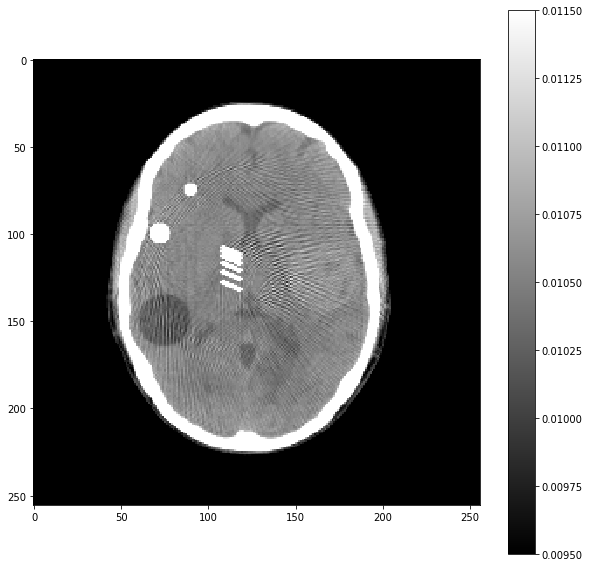

# Question 5

out = iradon(sinogram, theta=theta, circle=True)

plt.imshow(out,vmin=0,vmax=0.25)

plt.colorbar()

1

<matplotlib.colorbar.Colorbar at 0x7fce5a3361f0>

On se propose de comprendre l’origine de ces artefacts (dits de durcissement de faisceau).